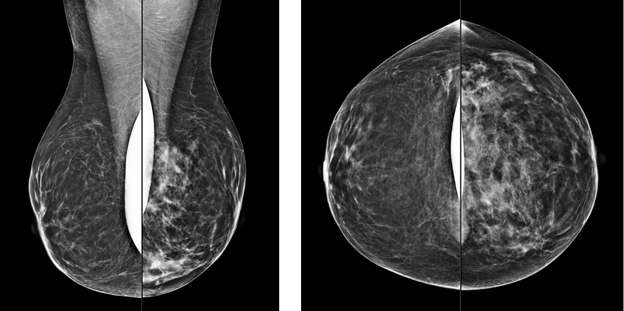

Global Asymmetry:

A global asymmetry is a finding seen on two projections of significantlyincreased breast tissue occupying greater than one quadrant. Global asymmetries that have been evaluated without suspicious features are most lynormal variantsand do not require additional follow up.